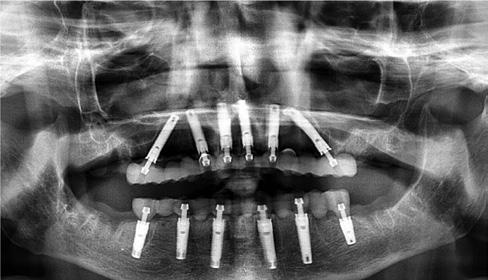

The following real case illustrates the workflow for a patient who was treated with full dentures in Abro Basic Multistratum and Denture Gingiva Basic Mono Pink.

Treatment plan

T he initial situation presented an edentulous upper jaw and a lower jaw with only the presence of tooth 43. The restorative team opted for two full dentures in Abro Basic Multistratum and Denture Gingiva Basic Mono Pink and a non-invasive zirconia crown restoration for tooth 43 with Prettau® 3 Dispersive®

Figure 4a. Before.

Figure 4b. After.